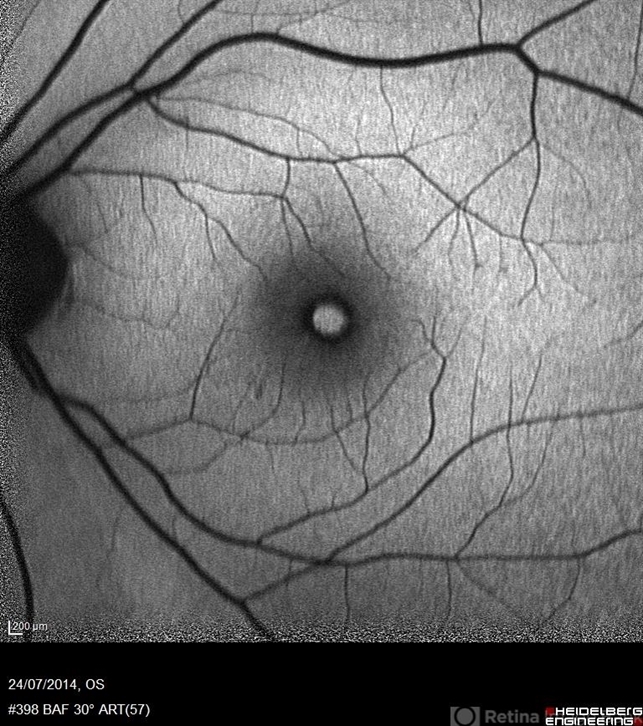

- macular hole, autofluorescence imaging

- Avris Romario Diparaja Siahaan, Klinik Mata Nusantara

Scanning laser ophthalmoscope

Heidelberg Spectralis - Description

- Autofluorescence image of a 55-year-old-woman with macular hole on her right eye.